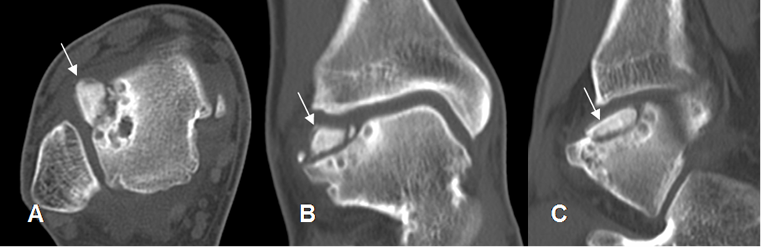

Fig 41. Lesión osteocondral estado IV.

A: TAC axial, B: TAC reconstrucción coronal y C: TAC reconstrucción sagital. Lesión osteocondral en la parte superoexterna del talo, con gran fragmento óseo desprendido.